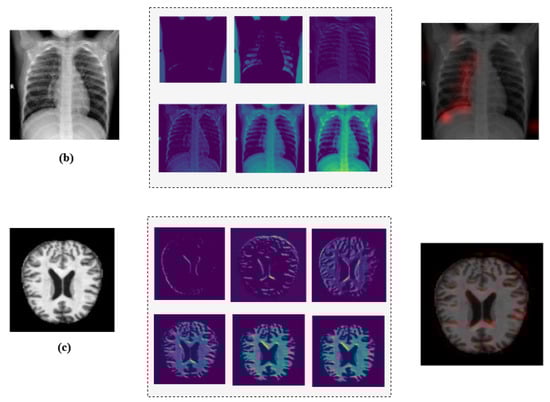

One way to artificially expand the amount and complexity of current data is through data augmentation [53]. To give developers access to more representative training data, data augmentation techniques have been used to increase the size of training sets [54,55]. In this study, we have applied different techniques for data augmentation to enhance the diversity of the datasets and to achieve a balanced distribution of classes, as in the example illustrated in Figure 2. The augmentation methods that we have employed include rotation, horizontal and vertical flipping, and other transformations to simulate different perspectives and conditions with the parameters summarized in Table 2.

Figure 2.

Illustration of applied data augmentation techniques.